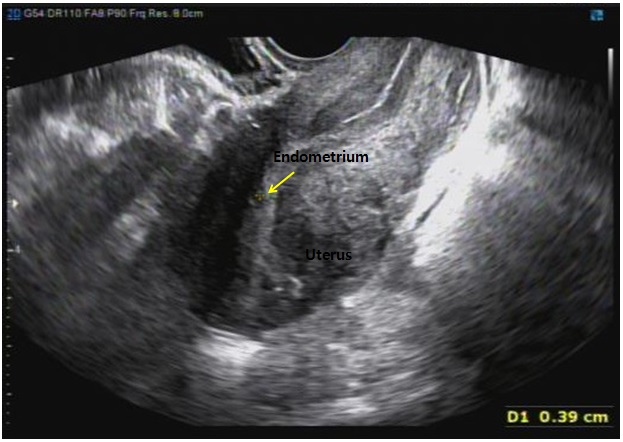

A 34-year-old woman, was 31 weeks and 4 days pregnant when she visited the emergency room with chief symptoms of abdominal pain and diarrhea for 3 days. She had undergone laparoscopic RFA for adenomyosis via M-1004 (RF Medical, Seoul, Korea) at a local hospital about three years prior. The patient succeeded in pregnancy after receiving in vitro fertilization and embryo transfer at a local infertility clinic and received regular checkups at another local hospital. She had abdominal pain three days before she visited and was taking a medication for enteritis because no special abnormal signs were found. She took the medicine; however, her symptoms gradually worsened. Her pain persisted, and she had a soft stool almost every hour. When she arrived at the emergency room, her vital signs were blood pressure 118/82 mmHg, body temperature 36.7 ℃, heart rate 101 beats/min, and respiratory rate 20 breaths/min. A blood test showed Hb 12.9 g/dL, WBC 7830/μL, platelet 173,000/μL, and CRP slightly increased to 1.0 mg/dL. There was no electrolyte imbalance, and otherwise no unusual test results. A fetal sonography showed the fetus presenting as vertex and the expected fetal weight was 1457 grams. The amniotic fluid index (AFI) was 9.7, an appropriate value, and the cervical length was 3.3 cm, with a T-shape. There was no leakage or pooling observed during the pelvic examination, and both the nitrazine and premature rupture of membrane (PROM) kit tests were negative. The fetal heartbeat was active, and uterine contractions appeared every 2 to 3 minutes during fetal cardiotoco-monitoring. After administration of the tocolytics, the patient symptoms improved; however, the patient complained of abrupt abdominal pain. The entire abdomen was tender; however, subplacental hematoma via ultrasound was not observed. Recurrent variable deceleration was observed without a uterine contraction in the cardiotocography (Figure 1); therefore, we performed an emergency cesarean section under the diagnosis of fetal distress. A large amount of blood and clots in the abdominal cavity was observed. A female baby was born, weighting 1.43 kg, with a 1 minute Apgar score of 4 and 5 minute Apgar score of 7. Placenta percreta with active bleeding was observed on the posterior wall of the uterus, and multiple lesions of placental percreta were also observed on the fundus, anterior, and posterior uterine wall (Figure 2). We experienced difficulty completely removing the placental invasion tissue, first considering that the severe adhesion was detected on the posterior uterine wall and the intestine. Therefore, we partially removed the placenta tissues and placed hemostatic sutures at the percreta sites, with two layers. The bleeding decreased, and the operation was completed while preserving the uterus. The patient was discharged from the hospital with a good overall condition on the seventh day after surgery. In the outpatient follow-up 6 months and 8 months after discharge, the posterior wall of the uterus had recovered, as shown via ultrasonography (Figure 3).

Figure 3.

Figure 3.— The endometrium (arrow) was observed in normal form on ultrasound, which was performed six months.